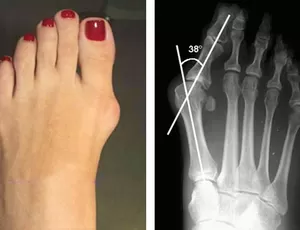

ESPORÃO

O esporão de calcâneo, também conhecido como esporão do calcanhar, é uma condição dolorosa que ocorre devido a um crescimento ósseo anormal na parte inferior do osso do calcanhar, chamado de calcâneo. Esse crescimento ósseo é geralmente resultado de tensão crônica nos ligamentos e músculos que se prendem ao osso do calcanhar, causando inflamação e dor.

O diagnóstico do esporão de calcâneo geralmente é feito com base nos sintomas relatados pelo paciente, exame físico e, às vezes, exames de imagem, como radiografias. Os raios-X podem mostrar a presença do esporão ósseo no calcanhar, embora nem todos os pacientes com dor no calcanhar tenham um esporão visível nas radiografias.